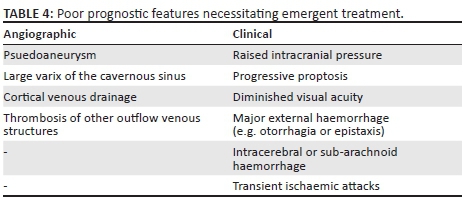

Ideal management involves occlusion of the fistula whilst ensuring the affected ICA remains patent. Conservative treatment is reserved for patients with indirect CCFs and who have tolerable and few symptoms. For all other fistulas requiring intervention, occlusion via endovascular means is the preferred method.3 To accomplish this, agents such as detachable balloons, coils, embolic materials and stents can be utilised via a transarterial or transvenous route.10 If the fistula cannot be occluded, sacrifice of the affected ICA may be required. Surgical treatment is reserved when the endovascular approach is unsuccessful. Emergent intervention is sometimes required if angiographic or clinically poor prognostic features are present (see Table 4).9